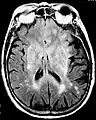

Axial fluid-attenuated inversion recovery MRI image demonstrating tumor-related infiltration involving lenticular nuclei (Arrow).

Axial fluid-attenuated inversion recovery MRI image demonstrating tumor-related infiltration involving both temporal lobes (Short arrow), and the substantia nigra (Long arrow).